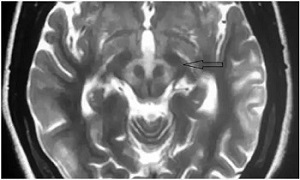

在查房的间隙,教授便在走廊里继续开讲起“走廊课堂”——“何谓熊猫征”来。教授说,“熊猫征”主要有“大熊猫脸征”和“小熊猫脸征”。其中,“大熊猫脸征”,红核在T2WI上呈现对称性的低信号,为大熊猫的眼,红核周围的内侧丘系、大脑脚上部、红核脊髓束及皮质脑干束神经纤维受累表现为T2高信号, 构成大熊猫脸上半部白色的轮廓;而双侧上丘、中脑导水管周围灰质神经核团正常的短T2信号及中脑导水管的长T2信号构成了大熊猫脸的下半部。

教授接着说,“小熊猫脸征”,中脑下部层面的双侧大脑脚、 上丘、 导水管、 导水管周围灰质核团、中央上核等构成了小熊猫脸的大体结构, 而双侧受累而呈长T2 信号的红核周围纤维束与短T2的中央被盖束勾勒出小熊猫的双眼。

教授说,熊猫征绝大多数为Wilson病(肝豆状核变性)的典型特征,也有个案报道见于Leigh病(亚急性坏死性脑脊髓病)。